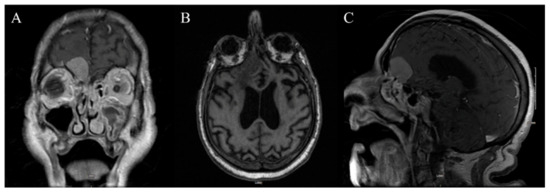

3.2. Case 2

3.2.1. Demography, Presentation, and Evaluation

3.2.2. Intervention

3.2.3. Postoperative Period